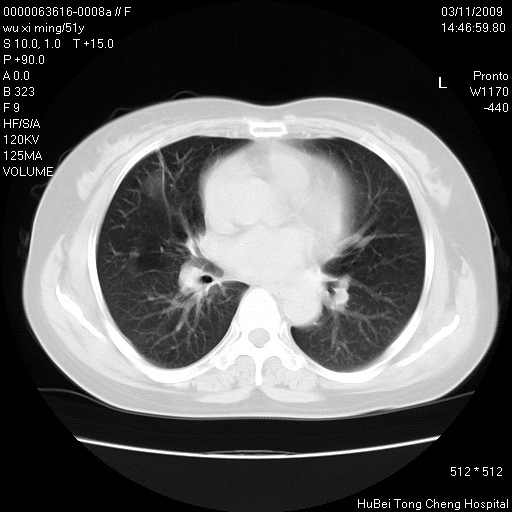

患者 女,51岁。因“胆囊炎,胆囊结石”,行常规术前胸部x线检查发现:右上肺结节病灶,建议行进一步检查。患者无咳嗽、咳痰及咯血等呼吸道症状,近期出现背部疼痛不适。

胸部ct轴位平扫(层厚10mm,螺距1.5,重建间隔10mm;部分层面:层厚3mm,螺距1.0,重建间隔3mm),图像如下:

考虑右肺癌肺内转移!

右肺周围型肺癌伴肺内转移信胸椎转移

右肺周围型肺癌伴肺内转移及胸椎转移。已无手术机会。